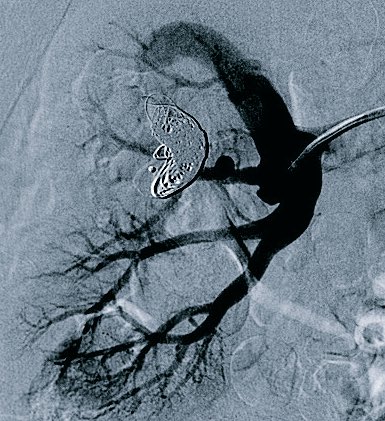

porto-systemic shunt- trans-hepatic access- 2 hrs,43 coils,2 plugs- @SIRRFS #irad #foamir #kitchensink #emptyshelves